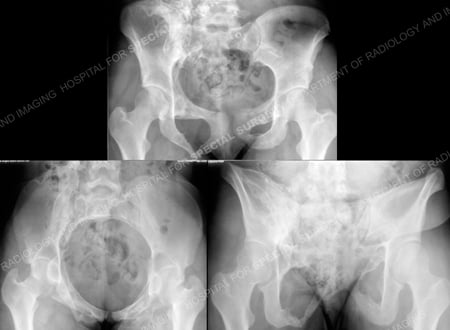

Pelvic radiographs including AP, inlet and outlet views (from top to bottom) at 19 months.

Pelvic radiographic x-rays 3 months following removal of hardware (and 22 months following the injury).